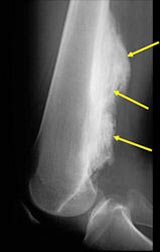

• • The work-up often consists of a physical examination, X-ray, MRI, and CT scans.

Radiographic imaging is used to help form a diagnosis. These include X-Ray, MRI, CT.